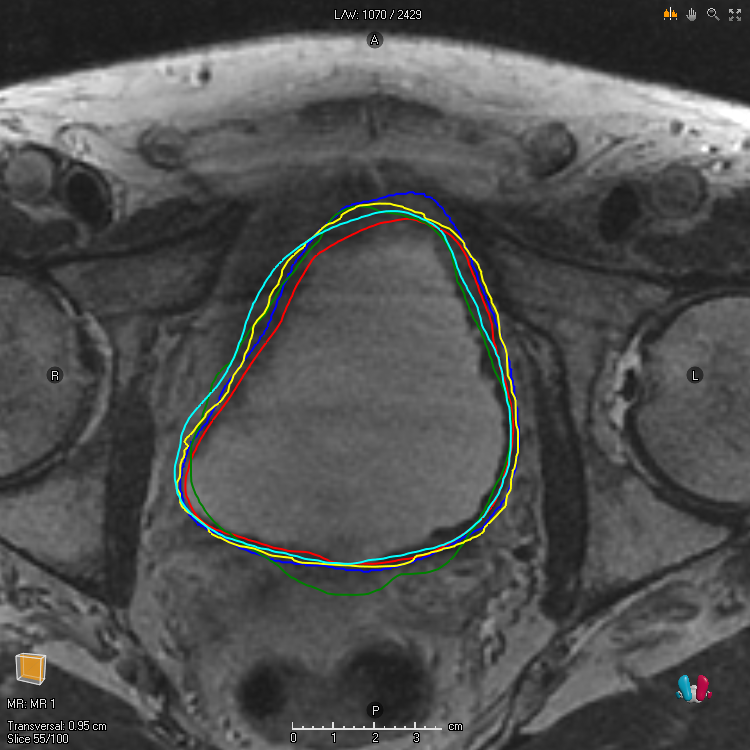

For a noisy segmentation L𝐿L, that is, a random variable taking values in 𝒮𝒮\mathcal{S}, m𝑚m can be taken to be the exact marginal success probability m(ω)=𝔼[L(ω)],ωΩformulae-sequence𝑚𝜔𝔼delimited-[]𝐿𝜔𝜔Ωm(\omega)=\mathbb{E}[L(\omega)],\;\omega\in\Omega. Such marginal functions are important in theory but can rarely be obtained in practice. Alternative choices of marginal functions include finite sample approximations, that is, point-wise averages over finite observations of L𝐿L, and estimates of 𝔼[L]𝔼delimited-[]𝐿\mathbb{E}[L] according to a single annotator [15, 11, 31, 16, 17]. These choices of m𝑚m are important because they are sometimes used for training machine learning models. Finally, note that A𝔼[L](s)=𝔼[AL(s)]subscriptA𝔼delimited-[]𝐿𝑠𝔼delimited-[]subscriptA𝐿𝑠\mathrm{A}_{\mathbb{E}[L]}(s)=\mathbb{E}[\mathrm{A}_{L}(s)] and 𝔼[AL(s)]𝔼delimited-[]subscriptA𝐿𝑠\mathbb{E}[\mathrm{A}_{L}(s)] is a common alternative way of specifying the metric. For Dice, this sort of relationship does not hold in general D𝔼[L](s)𝔼[DL(s)]subscriptD𝔼delimited-[]𝐿𝑠𝔼delimited-[]subscriptD𝐿𝑠\mathrm{D}_{\mathbb{E}[L]}(s)\not=\mathbb{E}[\mathrm{D}_{L}(s)]. However, it does hold that D𝔼[L](s)=𝔼[DL(s)]subscriptD𝔼delimited-[]𝐿𝑠𝔼delimited-[]subscriptD𝐿𝑠\mathrm{D}_{\mathbb{E}[L]}(s)=\mathbb{E}[\mathrm{D}_{L}(s)] when the volume of the noisy labels is constant Var[L1]=0Vardelimited-[]subscriptdelimited-∥∥𝐿10\text{Var}[\lVert L\rVert_{1}]=0, and it holds approximately D𝔼[L](s)𝔼[DL(s)]subscriptD𝔼delimited-[]𝐿𝑠𝔼delimited-[]subscriptD𝐿𝑠\mathrm{D}_{\mathbb{E}[L]}(s)\approx\mathbb{E}[\mathrm{D}_{L}(s)] when the variance of the volume of the noisy labels is small Var[L1]0Vardelimited-[]subscriptdelimited-∥∥𝐿10\text{Var}[\lVert L\rVert_{1}]\approx 0, which is often the case in medical image segmentation applications. Examples of observations of a particular L𝐿L for a couple of different target structures are depicted in Figure 1.

Figure 1: To the left is Urinary bladder and to the right is Neurovascular bundles for one patient in the Gold Atlas data [25]. Each line is associated with the boundary of a segmentation produced by a particular annotator. The screenshots are taken with RayStation 12A (RaySearch Laboratories AB, Stockholm Sweden).